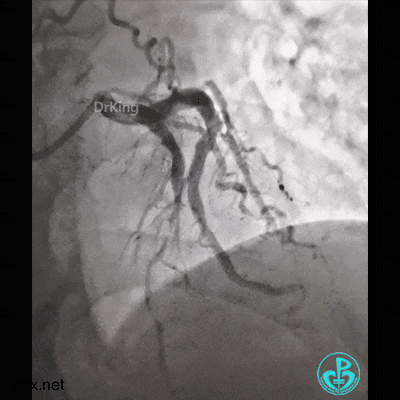

走左边,终于到位,造影。

左边EBU。

简单处理。

血运重建完成,胸痛缓解。生命体征平稳!